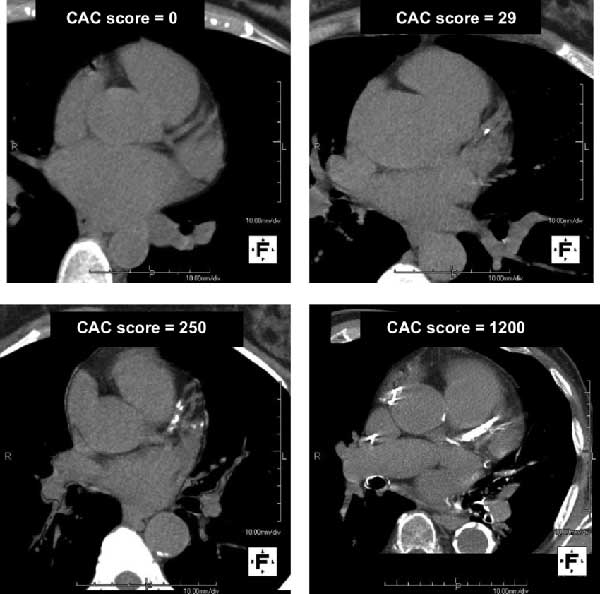

Calcium is a marker of Coronary Artery Disease. A Coronary Artery Calcium or CAC Scoring CT uses a low-dose CT scanner to detect and measure calcified plaque buildup inside the coronary arteries – producing a single number, your CAC Score, that reflects your overall cardiac risk. The exam is non-invasive, requires no injections, and is completed in minutes. Your score is then reviewed by one of our on-site radiologists and communicated to you and your physician to guide next steps.

- A radiologist measures calcified plaque buildup inside the arteries.

- Results are expressed as a CAC Score to help assess your overall cardiac risk.

Cardiac Calcium Scoring is used to assess cardiovascular risk in adults who have risk factors for heart disease but have not yet experienced symptoms. Studies have shown that CAC Scoring is a stronger predictor of heart disease than cholesterol levels alone. It can detect arterial plaque buildup before a heart attack or other cardiac event – giving patients and their physicians the information needed to make proactive decisions about lifestyle changes and medication.

During the exam, you lie comfortably on the CT imaging table and hold your breath for intervals of approximately 20 seconds while the scanner captures high-resolution images of your coronary arteries. The scan is fast, safe, and entirely non-invasive – no needles, no contrast dye, and no special preparation required. After the exam, one of our on-site radiologists reviews the images, identifies any areas of arterial calcification, and calculates your CAC Score.